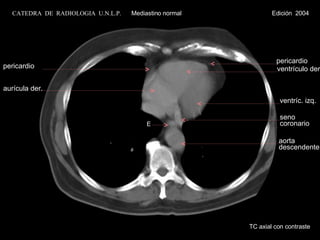

TC axial con contraste aurícula der. ventrículo der. ventríc. izq. E pericardio pericardio aorta descendente seno coronario CATEDRA  DE  RADIOLOGIA  U.N.L.P.   Mediastino normal  Edición  2004

TC axial concontraste aurícula der. ventrículo der. ventríc. izq. E pericardio pericardio aorta descendente seno coronario CATEDRA DE RADIOLOGIA U.N.L.P. Mediastino normal Edición 2004